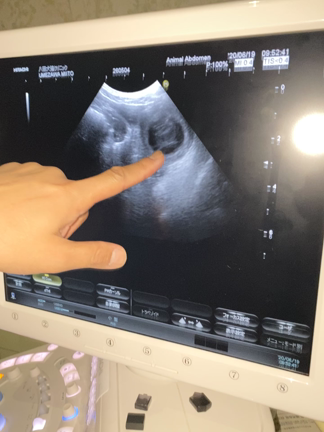

おなかPP